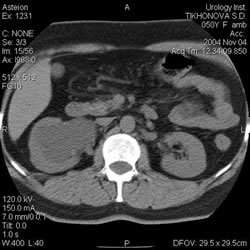

Компьютерная

томография: |

|